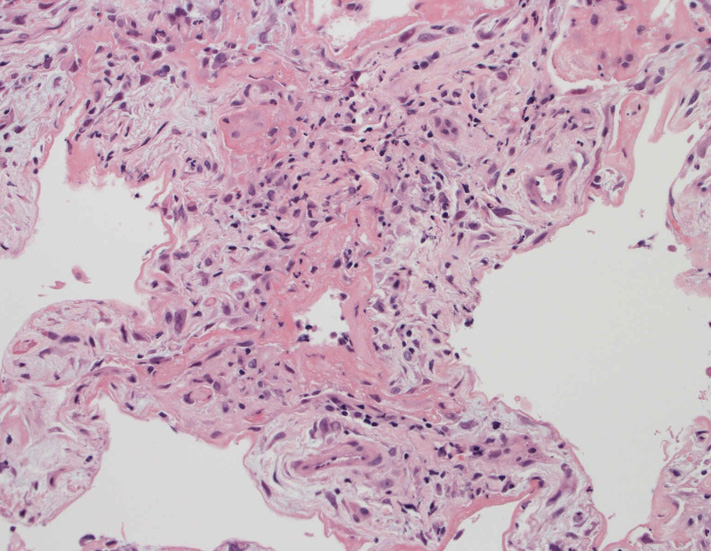

肺の病理所見

lung01.jpg

lung02.jpg

lung03.jpg

lung04.jpg

Fig.01Fig.02Fig.03Fig.04